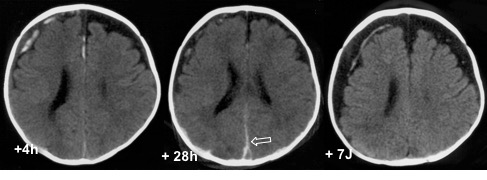

évolution temporelle

à la phase tout initiale, il existe des caillots à la convexité du cerveau, à proximité des veines en pont cortico-durales en regard du sinus sagittal.

dans les 24-48 heures on assiste à la migration des caillots sanguins, par gravité et/ou suivant le flux du LCS) vers :

- la faux du cerveau (qui s’épaissit)

- le sinus sagittal (signe du delta sous-dural)

- la tente du cervelet

dans le même temps, les caillots sanguins à la convexité s’amenuisent

on note également, dans les jours suivants l’apparition :

- d’une collection sous-durale hypodense (le LCS)

- d’une disjonction des sutures

cette évolution permet d’estimer une datation approximative du trauma. globalement, plus le saignement est abondant, plus le temps nécessaire à sa résorption est long ; plus l’évolution est rapide, plus on est proche du traumatisme.